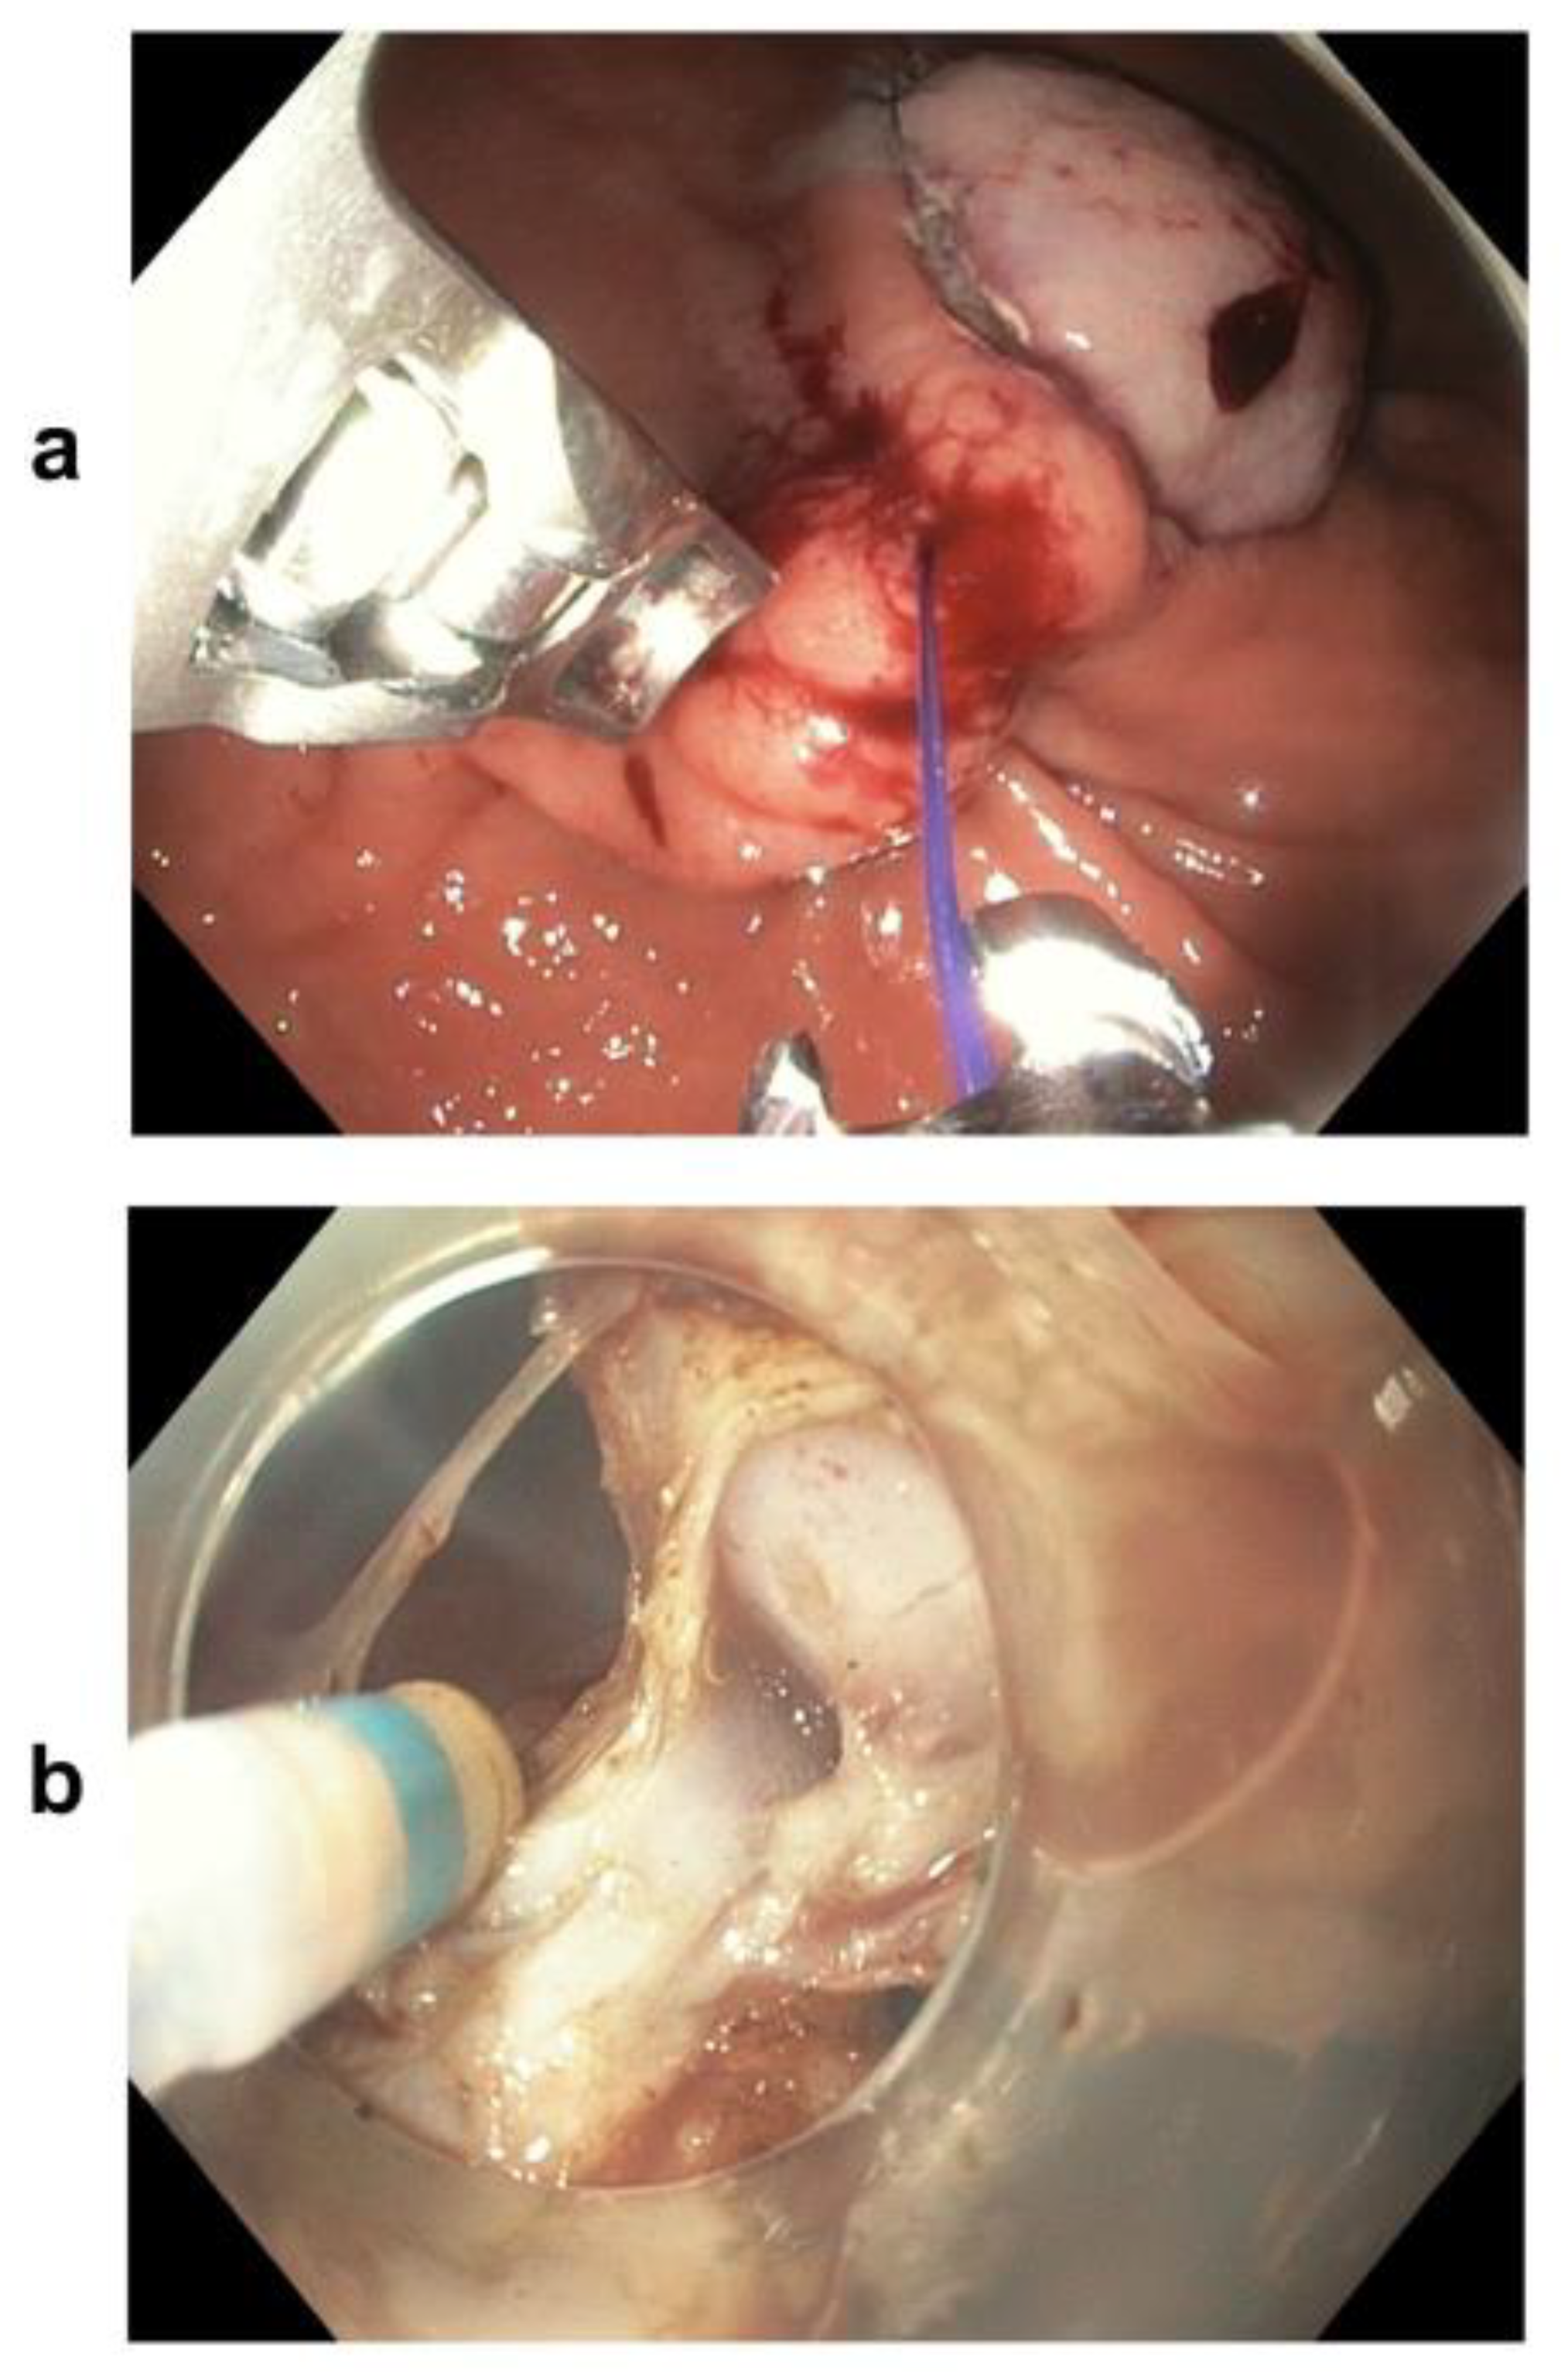

- The less invasive procedure includes various endoscopic resection techniques, such as ESD, EFTR, and STER.

- The hybrid technique combining endoscopic resection and endoluminal suturing appears to be a potential alternative for selected gastric GISTs with a large size and a high MP connection grade (type > I), with advantages over ESD.